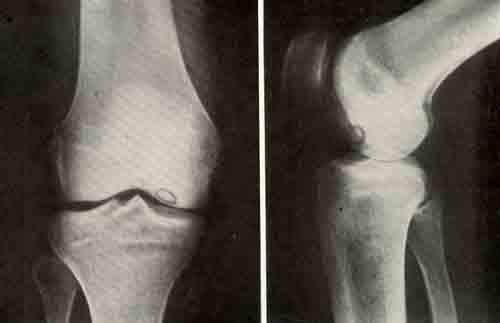

Эта форма остеохондропатии может продолжаться до 5 лет, и в некоторых случаях возможна инвалидность. Остеохондропатия коленного сустава развивается крайне редко.

Обследование

Прежде чем начинать лечение пациентов, необходимо точно установить диагноз. Для этого требуются следующие исследования:

- рентгенография;

- компьютерная томография (КТ) или магнитно-резонансная томография (МРТ);

- ультразвуковое исследование (УЗИ);

- электромиография.